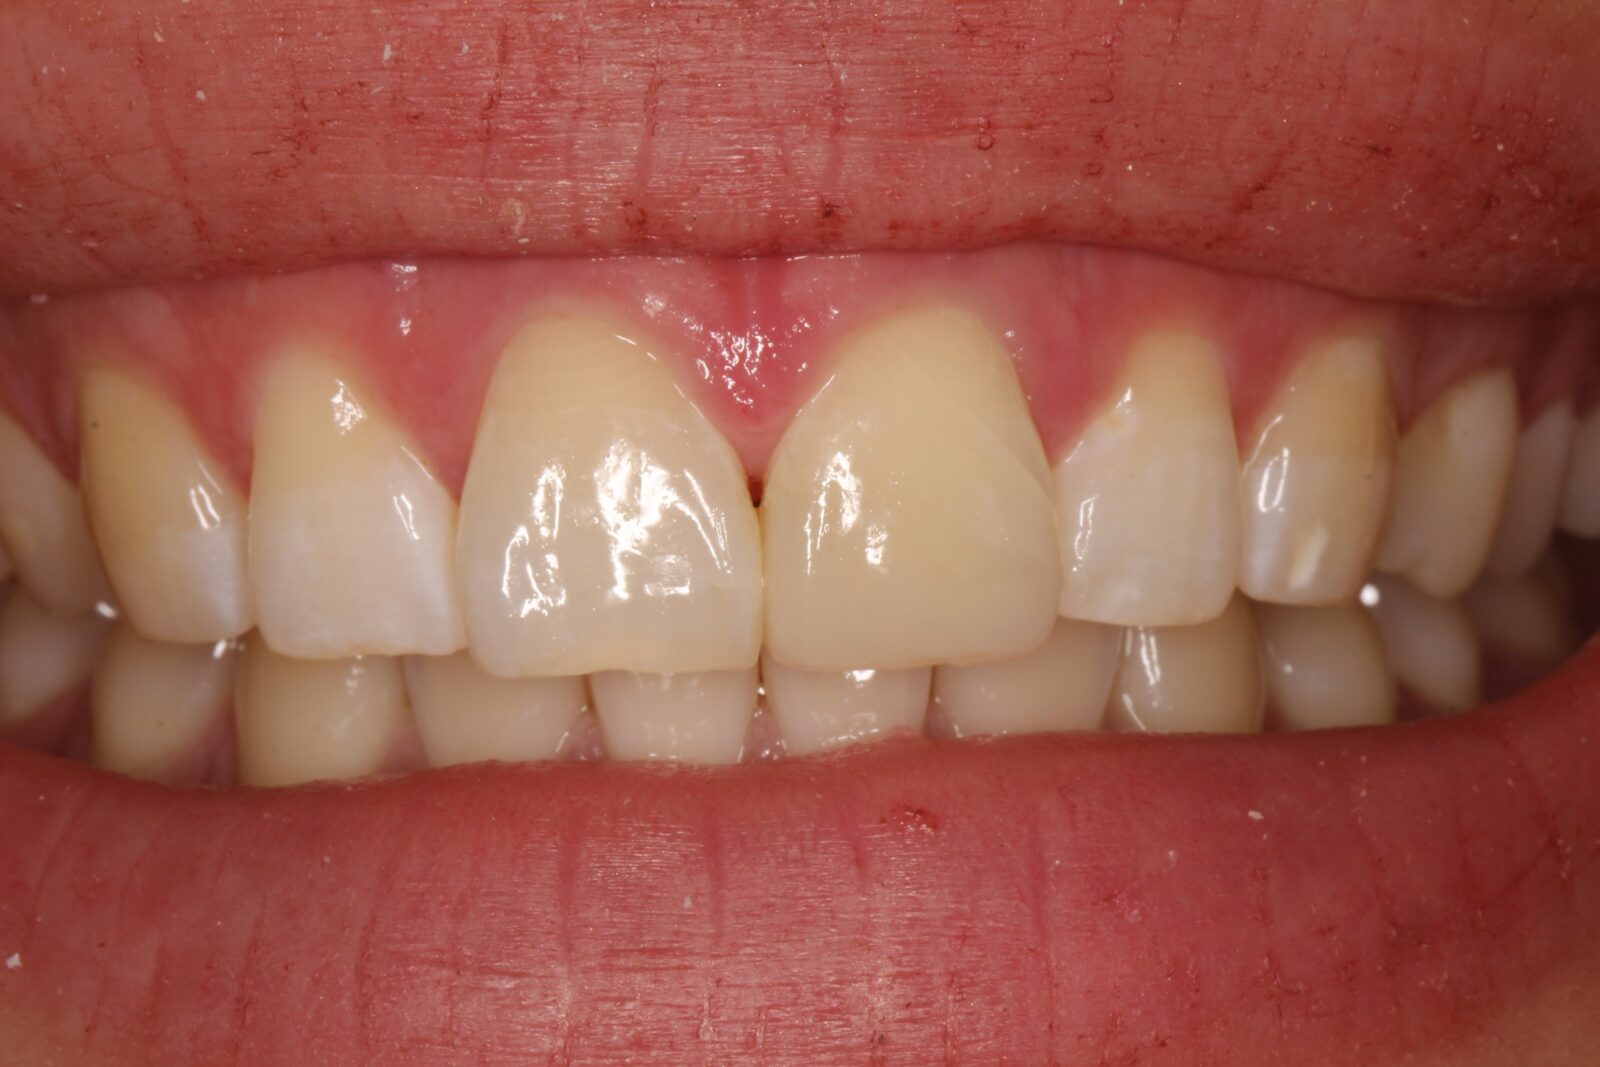

Внутриротовые фотографии 17.10.2022г